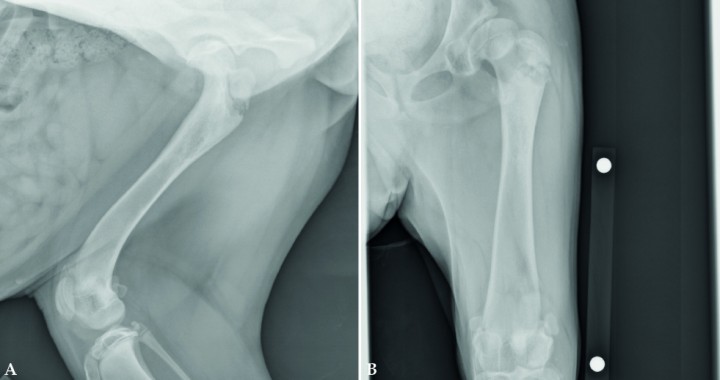

<p>Cuando no se realiza el diagnóstico de las fracturas de las líneas de crecimiento a tiempo, estas pueden tener consecuencias graves, incluso cuando las fracturas afectan a una prominencia ósea como el trocánter mayor del fémur. Radiografías de un cachorro de 6 meses de edad que presenta una no-unión de una fractura de la línea de crecimiento del trocánter mayor. En la proyección mediolateral del fémur (Fig. 8A) se observa esclerosis en la zona de la línea de crecimiento del trocánter mayor y signos de no-unión. En la proyección craneocaudal del fémur (Fig. 8B) se observa una no-unión y cambios degenerativos severos de la articulación de la cadera; estos son debidos a laxitud articular exacerbada por la pérdida de soporte muscular.</p>

Cuando no se realiza el diagnóstico de las fracturas de las líneas de crecimiento a tiempo, estas pueden tener consecuencias graves, incluso cuando las fracturas afectan a una prominencia ósea como el trocánter mayor del fémur. Radiografías de un cachorro de 6 meses de edad que presenta una no-unión de una fractura de la línea de crecimiento del trocánter mayor. En la proyección mediolateral del fémur (Fig. 8A) se observa esclerosis en la zona de la línea de crecimiento del trocánter mayor y signos de no-unión. En la proyección craneocaudal del fémur (Fig. 8B) se observa una no-unión y cambios degenerativos severos de la articulación de la cadera; estos son debidos a laxitud articular exacerbada por la pérdida de soporte muscular.